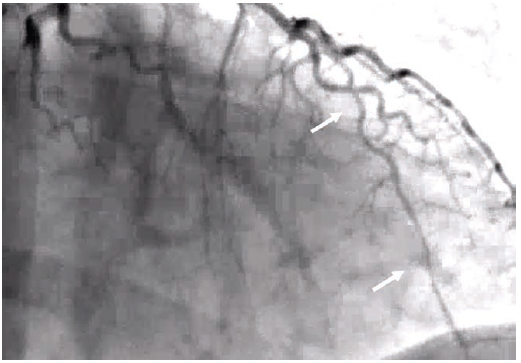

Patient 1 is a woman in her 50s, with chronic back pain, hypertension, and remote history of a transient ischemic attack (TIA). She presented to the emergency department with chest pain and elevated high sensitivity troponins >80,000 and was taken to the cath lab. She was found to have type II spontaneous coronary artery dissection in the mid to distal left anterior descending (LAD) coronary artery (Figures 1-2; Video 1). The right coronary artery (RCA) was normal. Of note, the patient had a similar presentation more than 1 year ago with high sensitivity troponins >16,000. The angiogram was normal (Figure 3; Video 2).

Jacqueline Saw, University of British Columbia, Vancouver, British Columbia: For patient 1, I urge you to relook at the high 1st diagonal artery on the 2022 angiogram. From the one angiogram projection that was provided, it looks like there is diffuse narrowing (type 2) SCAD of this high diagonal artery. Please look at other cranial projections to hunt for it. Also look for wall motion abnormality on the left ventriculogram. I assume there will be lateral hypokinesis corresponding to the high troponin >16,000. In fact, when you compared to the right anterior oblique (RAO) cranial angiogram of 2024, this high 1st diagonal is of larger caliber (healed).